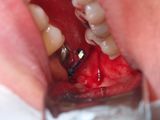

P9160003.JPG

Olympus TG-6

1/100s f/4.9 at 18.0mm iso200 full exif